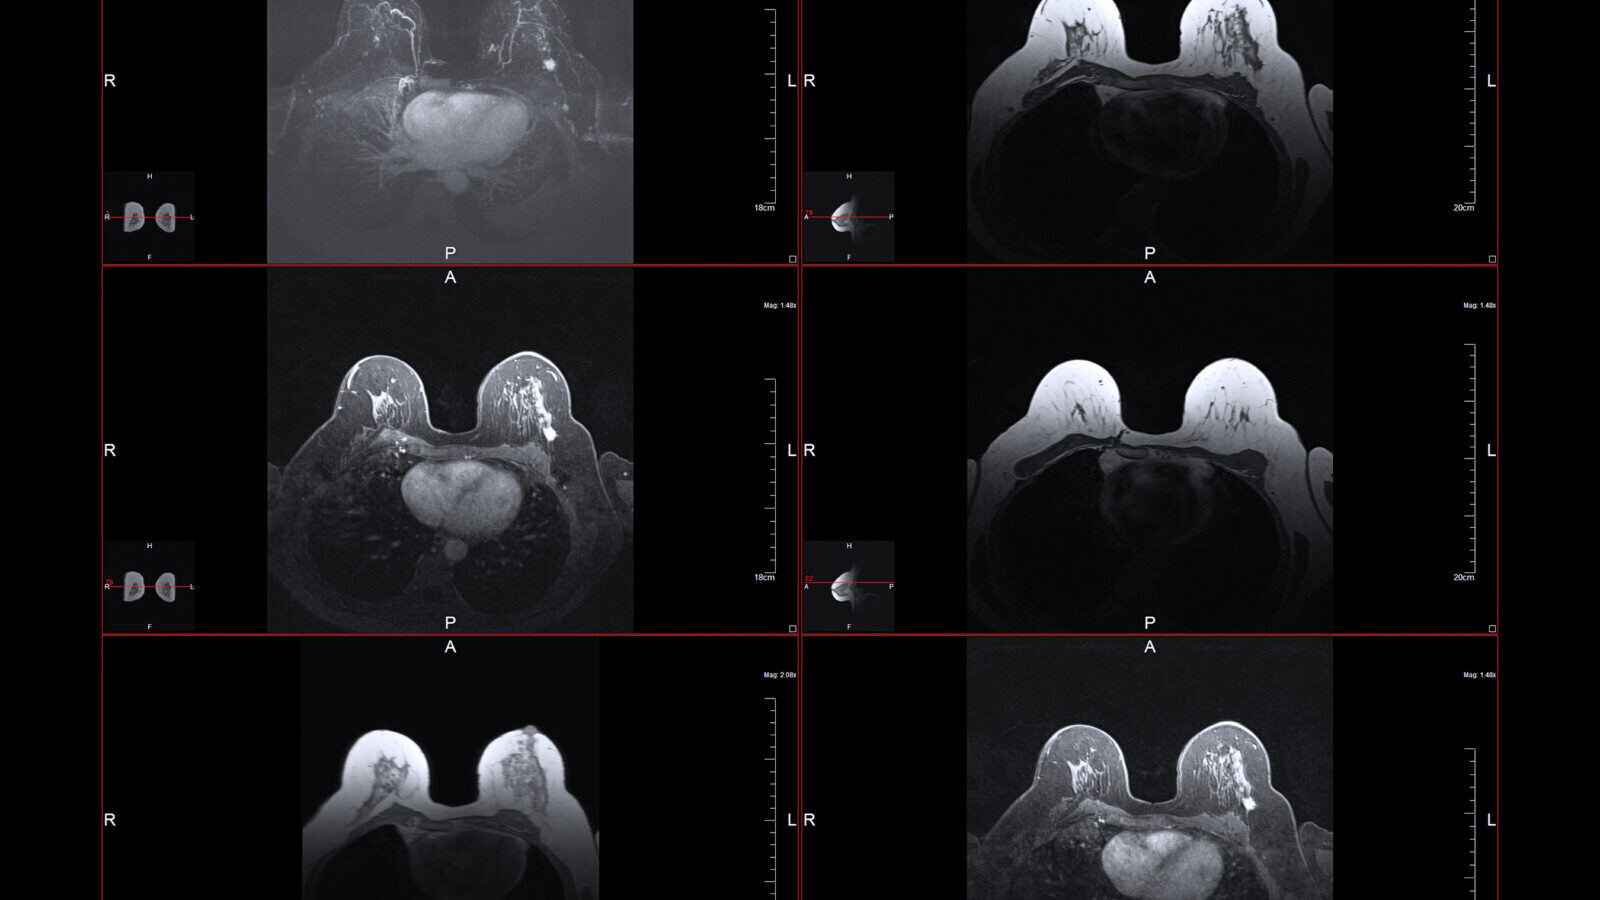

The bright white dot in the larger of these MRI images is Stage One breast cancer. (Adobe)

Breast cancer study reveals a paradox of mastectomy

"If you get a contralateral breast cancer, your risk of dying goes up. But preventing it doesn't improve your survival," said Steven Narod, a breast cancer researcher and physician at Women's College Hospital in Toronto and the lead author on the study. Read more.